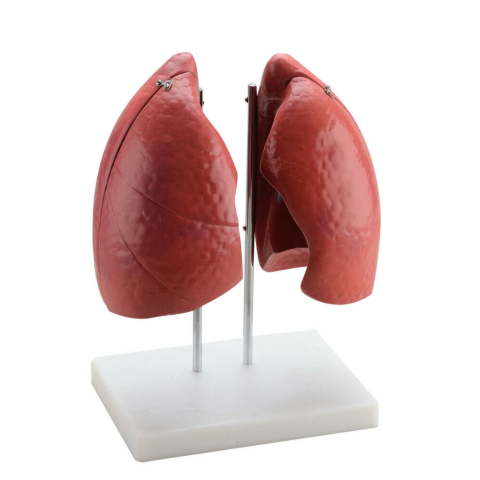

1 kép

1 kép OEM Anatómiai Tüdőmodell - 4 Rész - Élethű - 57x46x62cm

35 900 Ft-tól

Élethű 4 részes tüdőmodell: Tanulmányozd a légzőrendszer anatómiáját! 🫁 Ez az élethű tüdőmodell kiváló eszköz az emberi légzőrendszer részletes tanulmányozásához. Négy részből áll, így könnyedén megvizsgálhatóak a tüdőlebenyek, a vénák és az artériá...